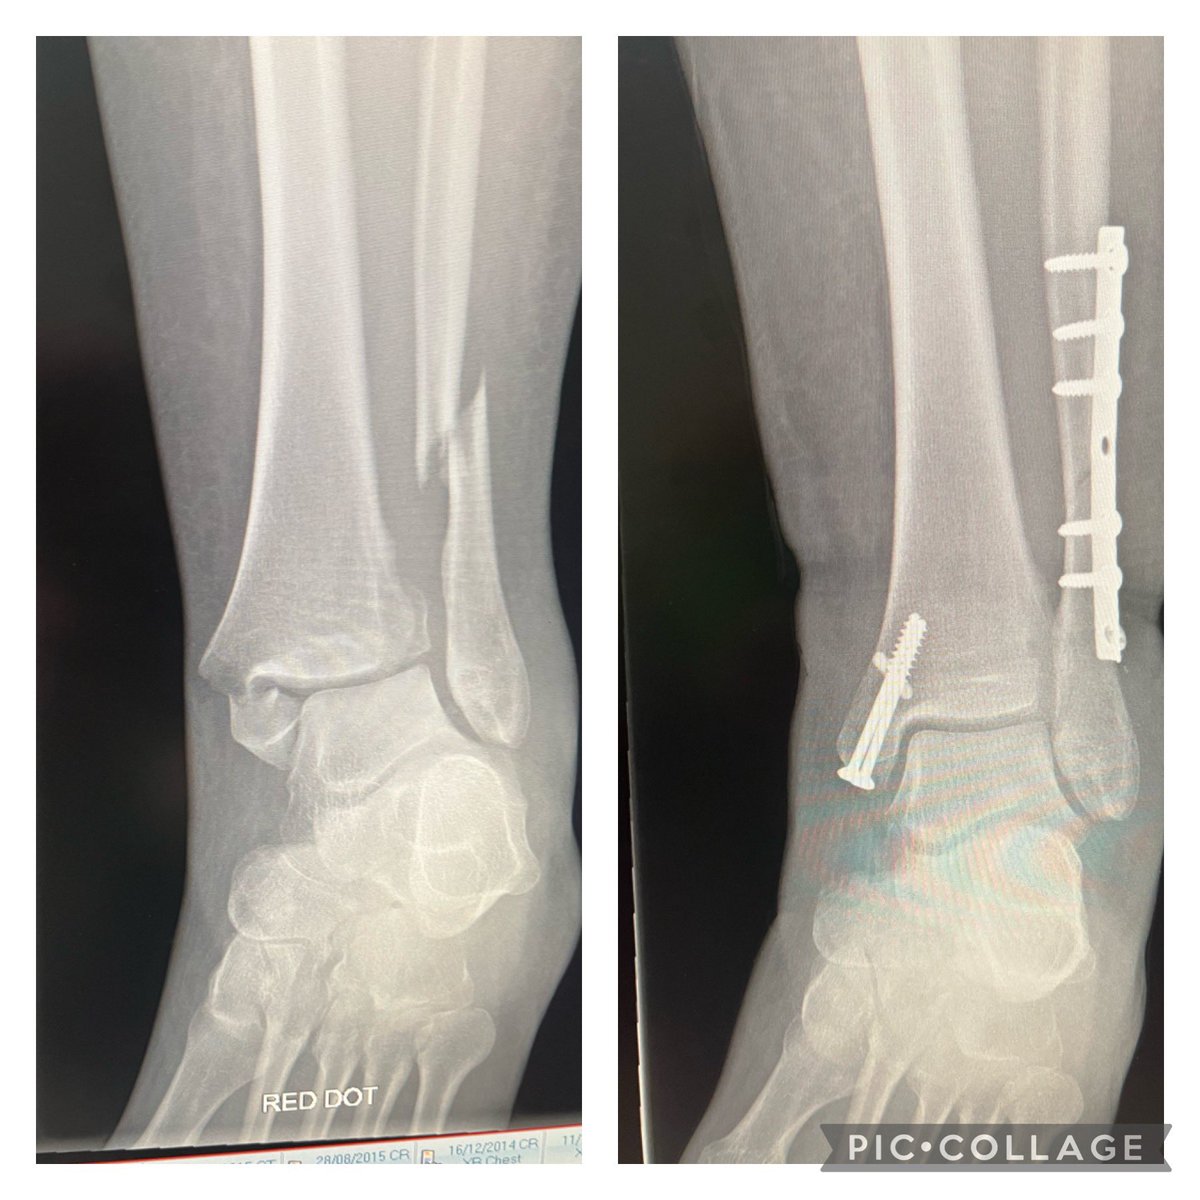

Before and after photos - disappointing to hear I still have a long road to recovery ahead. Am thankful for the care I have had @ninewellshospital